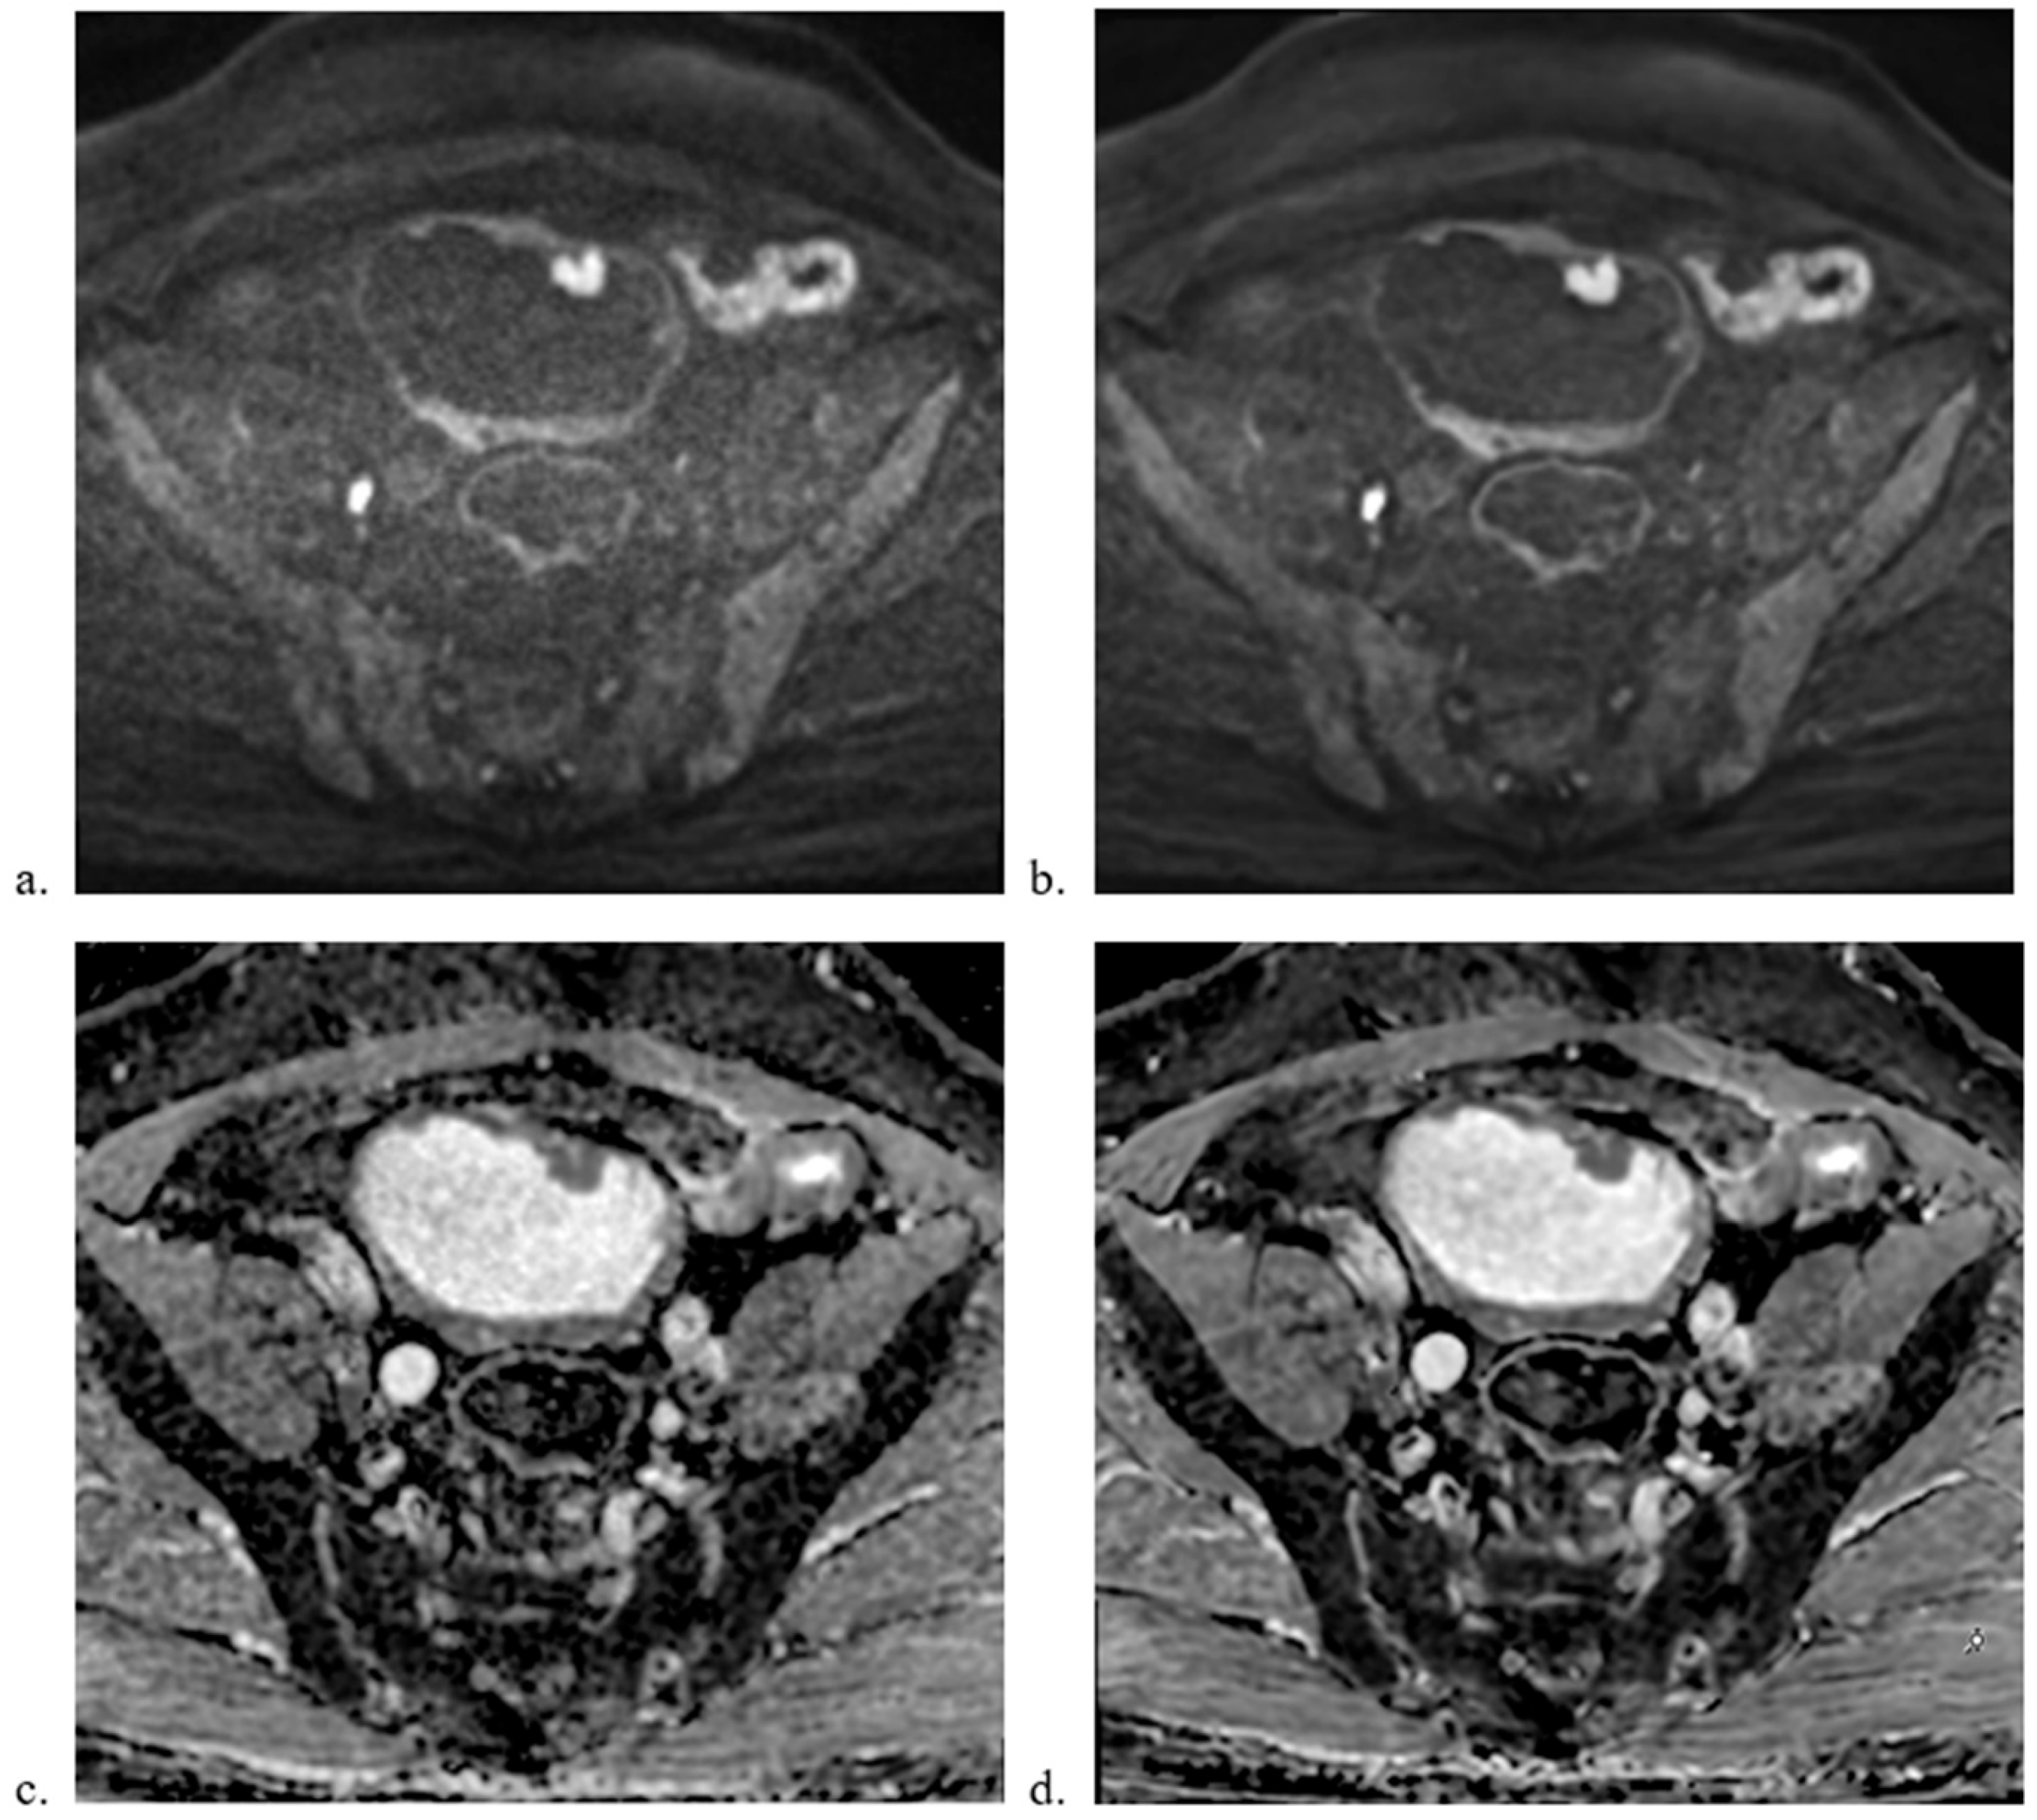

3.2. Qualitative Image Analysis

3.3. Quantitative Image Analysis